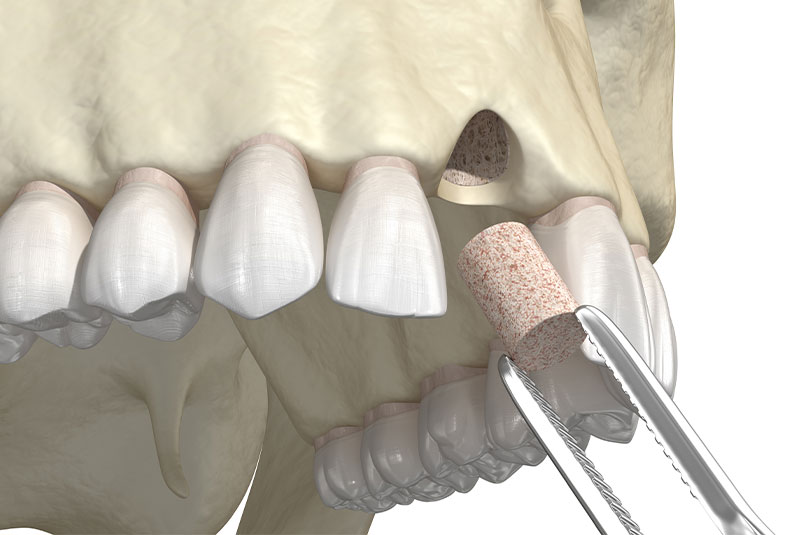

Bone grafting is a surgical procedure that involves placing dental bone graft material in areas where the bone has resorbed, or a tooth has been extracted. The purpose of bone grafting is to restore the proper density, height, and width of the bone in the jaw. Bone grafts can be either from the patient or from a donor source and may either be a bone block or granules. In many cases, we offer bone grafting treatment before we place dental implants or during implant surgery to ensure the long-term success of dental implants. Below are additional bone grafting techniques.

Socket Preservation

Socket preservation is a bone grafting procedure we complete after tooth extraction. This involves packing bone graft material into the empty tooth socket. Socket preservation slows the resorption process where the tooth is missing. It can also help preserve the health of the bone until a dental implant can be placed.